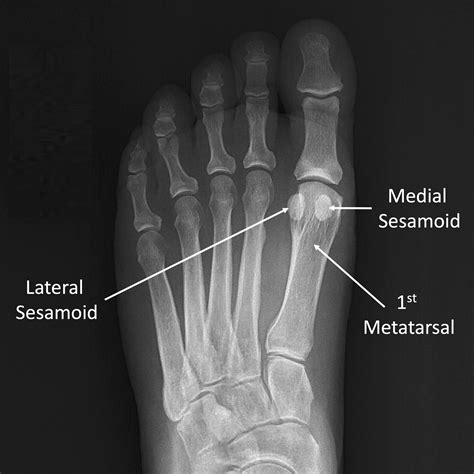

The sesamoid bones are small, round bones embedded within tendons. In the foot, there are two sesamoid bones located beneath the head of the first metatarsal bone, which is the long bone connected to the big toe. These bones are named the medial and lateral sesamoid bones, and they act as pulleys for the tendons that control the big toe.

• X-rays: To visualize the bones and detect any fractures or abnormalities.

• sesamoid bone foot xray